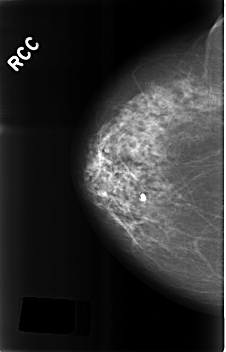

ics_version 1.0 filename C-0287-1 DATE_OF_STUDY 9 1 1995 PATIENT_AGE 89 FILM FILM_TYPE REGULAR DENSITY 2 DATE_DIGITIZED 4 8 1998 DIGITIZER LUMISYS LASER SEQUENCE LEFT_CC LINES 4592 PIXELS_PER_LINE 2960 BITS_PER_PIXEL 12 RESOLUTION 50 OVERLAY LEFT_MLO LINES 4584 PIXELS_PER_LINE 2976 BITS_PER_PIXEL 12 RESOLUTION 50 OVERLAY RIGHT_CC LINES 4568 PIXELS_PER_LINE 2928 BITS_PER_PIXEL 12 RESOLUTION 50 NON_OVERLAY RIGHT_MLO LINES 4600 PIXELS_PER_LINE 2904 BITS_PER_PIXEL 12 RESOLUTION 50 NON_OVERLAY |